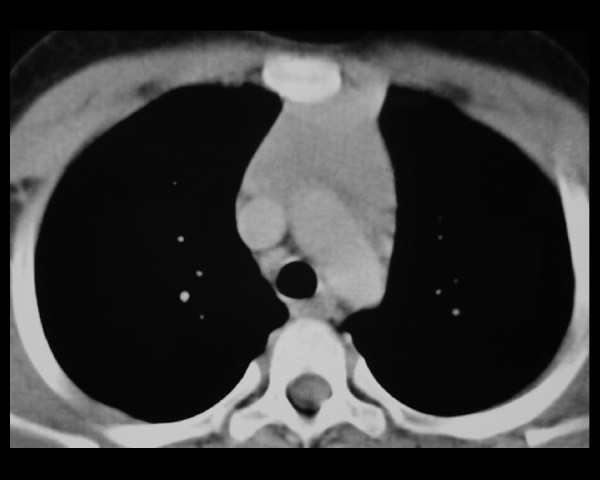

1397. Учитывая локализацию патологического образования средостения по данным томографического среза

а также наличие у пациентки миастении гравис, с целью удаления опухоли, целесообразно использование